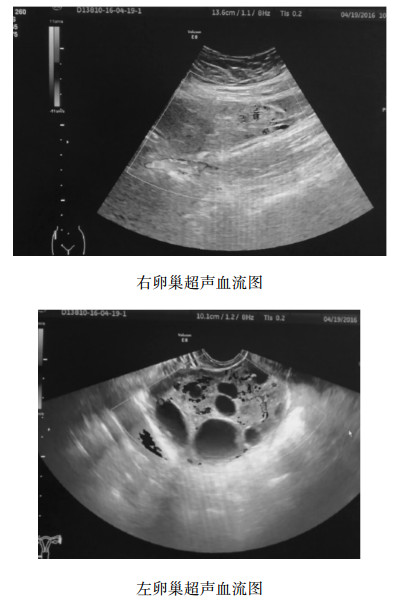

1.3 治疗明确诊断后,即嘱患者绝对卧床休息,同时予硫酸镁静滴保胎,经临床观察后腹痛无明显好转,即予积极完善各项术前检查后,予次日上午在全麻下行腹腔镜探查术。术中见右附件扭转,蒂部紧贴骨盆漏斗处扭转360°,右卵巢和输卵管肿胀呈暗紫色。因术前术中谈话患者及家属要求保留卵巢,复位后观察十余分钟,输卵管卵巢外观恢复血供。操作过程中避免碰触刺激子宫。术毕安返病房,卧床休息,予补液,预防感染,硫酸镁保胎,黄体酮肌注、达芙通口服黄体支持治疗。术后4dHCG 41 091 U/L,术后一周超声示子宫孕40 d大小,宫腔内见两个胚囊,内均见卵黄囊及胚芽,芽长分别为0.4 cm、0.5 cm, 均可探及心搏。右卵巢大小11.5 cm×7.3 cm×10.1 cm, 内呈多房囊性,未见明显血流信号。左卵巢7.1 cm×8.6 cm×5.7cm内呈多房囊性,血流较丰富。左右卵巢超声血流如图 2。

|

| 图 2 患者治疗后卵巢超声血流图 |

|

|